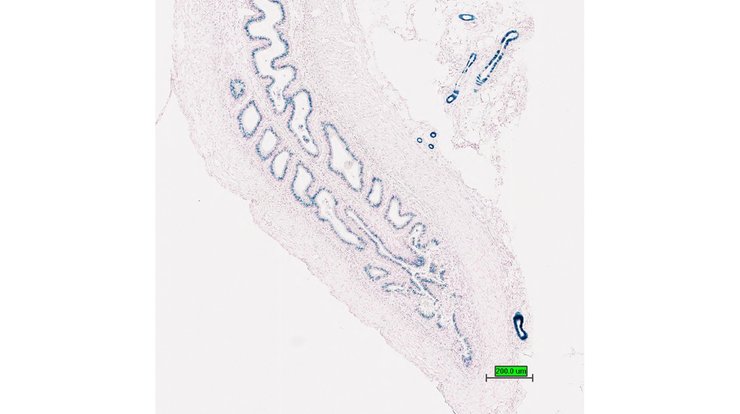

TS28: esophagus Present UC Davis_1883696

TS28: colon Present UC Davis_1883698

Specimen UC Davis_1883699: postnatal adult; Dmp1tm1.1(KOMP)Vlcg/Dmp1+ (more )

Structure Level Pattern Image Note

TS28: colon Present UC Davis_1883699

Specimen UC Davis_1883700: postnatal adult; Dmp1tm1.1(KOMP)Vlcg/Dmp1+ (more )

TS28: colon Present UC Davis_1883700

Specimen UC Davis_1883701: postnatal adult; Dmp1tm1.1(KOMP)Vlcg/Dmp1+ (more )

TS28: colon Present UC Davis_1883701

TS28: cecum Present UC Davis_1883702